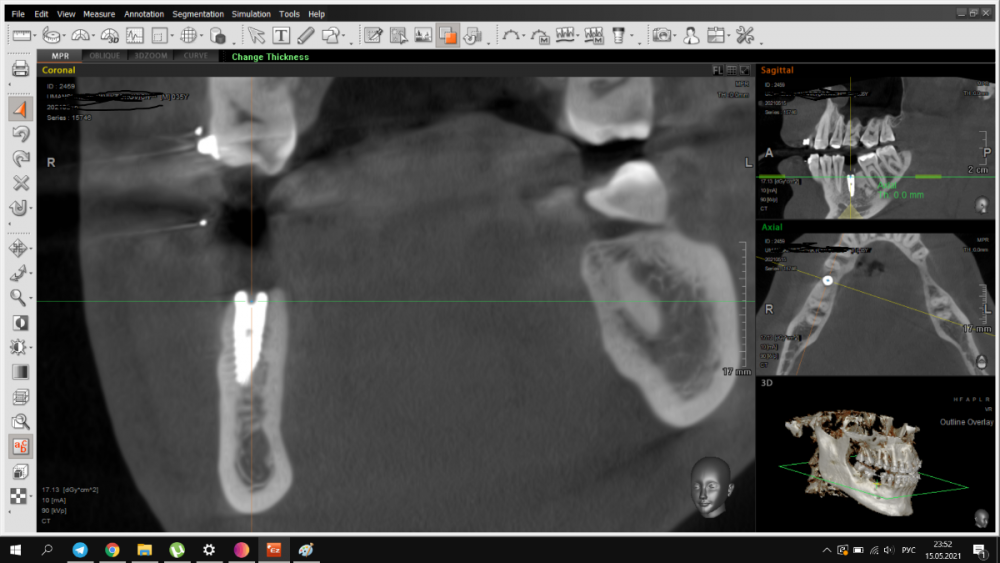

It'sGeorgy Опубликовано 15 мая, 2021 Автор Поделиться Опубликовано 15 мая, 2021 Пациент пропал на год, позвонил в клинику сегодня, отправили на кт. Сказал, на десне какой-то прыщик на десне(скорее всего, причина в этой оставленной штуки в десне) и что-то где-то там болит(сверху пульпит прям над винтом). В прошлых сообщениях забыл указать: графта не было. А вот имплантат откровенно неудачно поставил, надеюсь, десна вывезет. Да и сам имплантат, если бы сейчас ставил, выбрал Штрауманн ТЛ. 1 Ссылка на комментарий

It'sGeorgy Опубликовано 15 мая, 2021 Автор Поделиться Опубликовано 15 мая, 2021 Только что, Irouil сказал: А что,собственно, не нравится? ну язычнее надо бы...вестибулярная стенка у шейки совсем тонкая. Ну и десны после транспа с бугра много вышло, 5.5 мм по КТ(знаю, что это не всегда соответствует реальности, но все же). В таких случаях стараюсь полированной шейкой поддесневую часть выполнять, ибо любая недополировка абатмента или поддесневой части коронки будет критична. Ссылка на комментарий